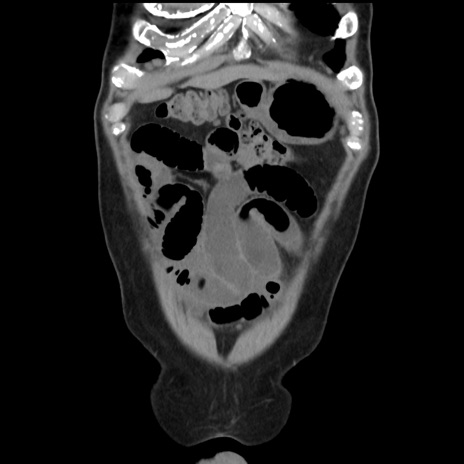

症例16(冠状断像)

【症例】 70歳代男性

【主訴】 腹痛、嘔吐

【現病歴】 約1ヶ月前より間欠的に腹痛と嘔吐あり、当院消化器内科を受診したところCTで多発する肝臓のLDAを指摘され、精査中であった。以降は消化器症状は安定していたが、2日前より嘔気と腹痛があり、同日より排便・排ガスが消失した。改善認めず、 本日、救急外来を受診した。